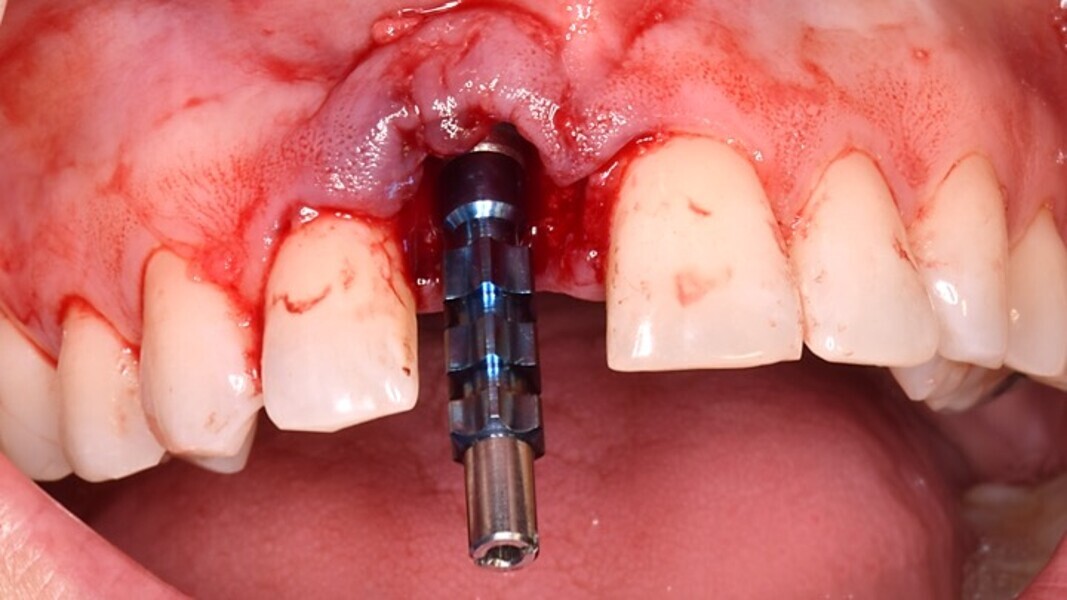

Figura 6. A pesar del defecto óseo, siempre buscamos la posibilidad de crear un nuevo alveolo quirúrgico que emerja por la zona del cíngulo de los dientes adyacentes, es decir, el margen de emergencia adecuado. En estos defectos, intentamos siempre el anclaje en profundidad con implantes largos de unos 16 mm debido al gran defecto existente. Es la única forma de que la estabilidad primaria del implante permita realizar una Prótesis Inmediata.

Figura 7. Implante de conexión interna insertado 2 mm por debajo de la cresta ósea, independientemente del defecto existente y a 55 Nw. Al no existir margen vestibular, tomamos como referencia los dos picos óseos de las papilas y entre ellos trazamos una línea imaginaria que los una enterrando el hombro unos 2 ó 3 mm por debajo de ella.